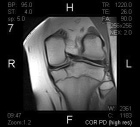

D.E. - 15 year old male with left knee pain after falling from a skateboard three weeks ago